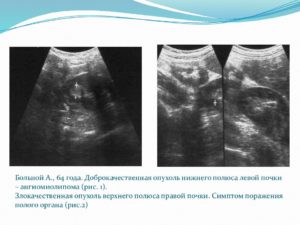

Это достаточно редкий вид доброкачественной опухоли почки, к образованию которой ведет врожденная мутация генов. Заболеванию в почти 80% случаев сопутствует туберозный склероз. Как и другие липомы почек, ангимиолипома поражает жировую ткань почки – именно здесь клетки начинают бесконтрольно делиться.

Образование может встречаться и в качестве одиночной болезни. Наиболее подвержены риску его развития женщины среднего возраста. Обычно опухоль бывает незначительных размеров и мало беспокоит пациента. Это обуславливает тот факт, что диагностируют ее чаще всего случайно.